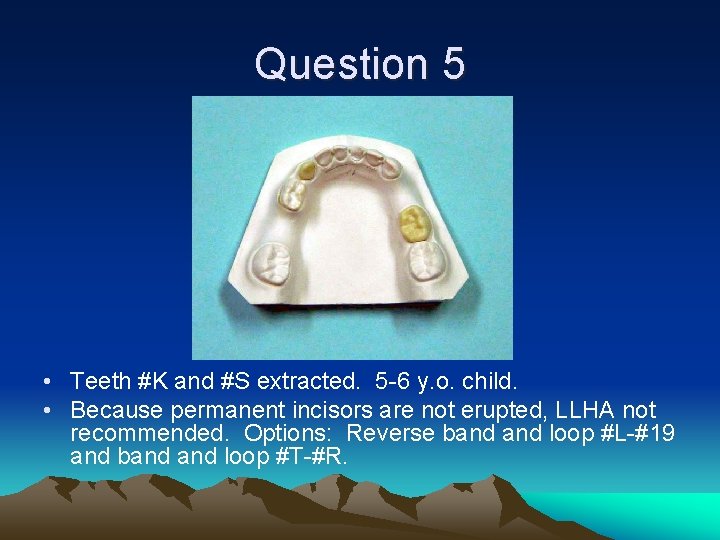

Question 5 • Which teeth have been extracted? How old is the child? • What is the most appropriate space maintenance?

Question 5 • Teeth #K and #S extracted. 5 -6 y. o. child. • Because permanent incisors are not erupted, LLHA not recommended. Options: Reverse band loop #L-#19 and band loop #T-#R.